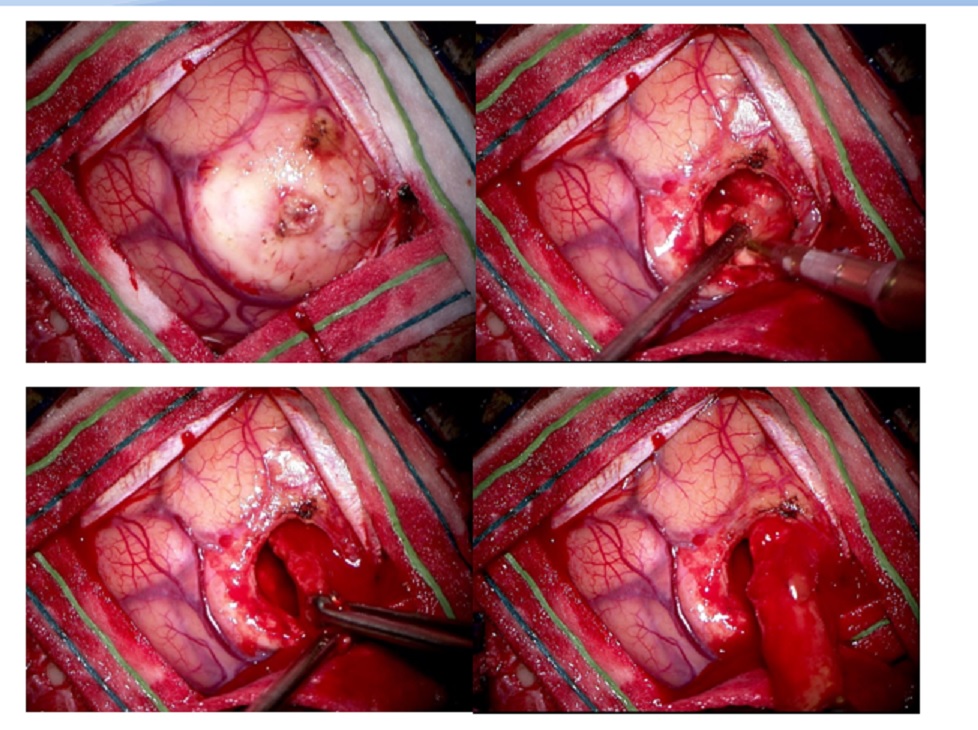

The Stealth coordinates in my Brain having been calculated, I had to land at the precise location which was the dome of the tumour, lock on to the tumour exposing it, use all resources I had to excise the tumour and escape undetected by P’s Brain – The Perfect ‘No-touch’ Technique.

For decades we were taught as residents to mark out the eloquent areas of the brain. Like I said in this case it would be the Motor strip. I was fortunate that I could land on the chosen spot.

The gyrus overlying the tumour was obviously widened and broad. Aspiration yielded a haemorrhagic fluid. The tumour was encapsulated and could be delivered as a whole. But there was an area on the posterior superior aspect which was greyish red with sheaves of blood vessels coursing through it which still could be Glioma.

Dr. Houda provided excellent anaesthesia with a lax brain. I packed the tumour cavity with cotton balls to show that only the brain tumour was excised. Not a single millimetre of the normal cortex was touched. She recovered well and the right hemiparesis resolved within hours of surgery. Thanks to the ICU Team of Drs. Anas and Khamis; for close monitoring of the case preoperatively and postoperatively. These cases are tricky with a proclivity for sudden loss of consciousness due to hemorrhage in the Cystic tumour.